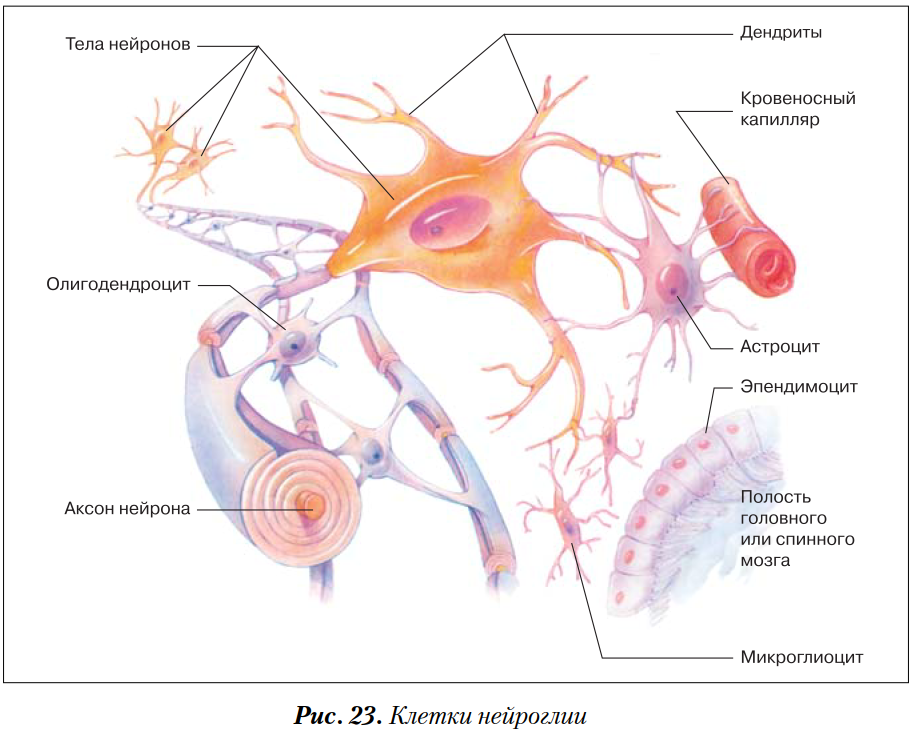

Мир нейроцитов: исследование нервных клеток

Раздел: Необычные решения